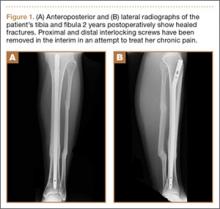

Approximately 1 year after her initial injury, the patient began to complain of progressive and persistent anteromedial knee pain as well as gradual-onset, medial-sided leg pain. The leg pain began at the level of her previous fracture site, at the distal one-third metadiaphyseal tibial junction, and radiated from the site of her previous medial open wound distally to the medial aspect of her foot. The pain was burning and tingling in nature, with associated hyperesthesia of the affected area. A diagnosis of CRPS was made, and the patient was prescribed a course of desensitization therapy, oral neuromodulating agents, and physical therapy. After 3 months’ therapy, she remained symptomatic and underwent removal of her proximal tibial interlocking screw fixation (Figure 1). When these measures failed to provide symptomatic relief, and having seen several therapists and physicians, including physiatrists, pain management specialists, and orthopedic surgeons, she presented to our clinic for consultation.